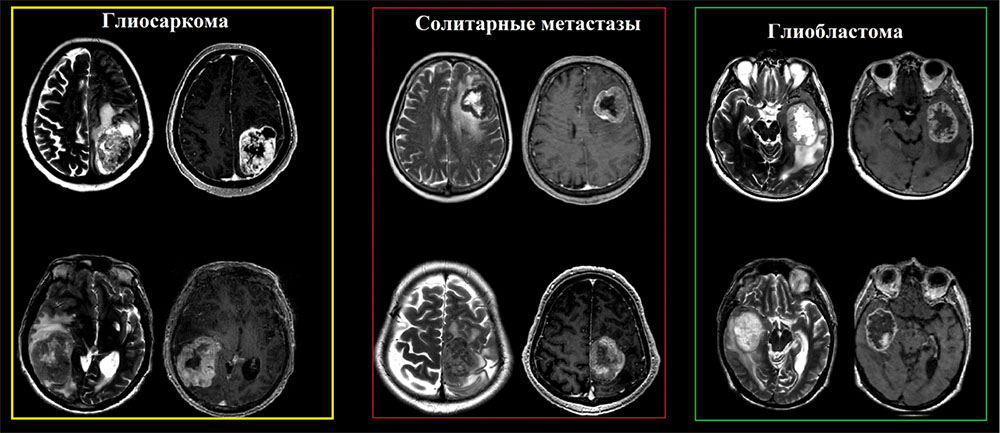

Частота встречаемости глиосарком составляет от 1% до 8% от всех злокачественных глиом, пик встречаемости 4-6 декады жизни с преобладанием мужской популяции, с медианой выживаемости около 9 месяцев. Глиосаркомы имеют общие и практически не отличимые визуализационные характеристики в сравнении с классическими глиобластомами и в большинстве случаев диагноз устанавливается после иммуногистохимического исследования. Стоит отметить, что глиосаркома обладает более высокой тенденцией к экстракраниальному метастазированию (наблюдаются в 30% случаев), последние включают висцеральные органы и спинной мозг.

Глиосаркома должна быть включена в дифференциальный ряд любой опухоли, которая, по-видимому, является интрааксиальной, но при этом «интимно» прилежит к твердой мозговой оболочки  и демонстрирует гетерогенные визуализационные характеристики на T2-взвешенных изображениях.